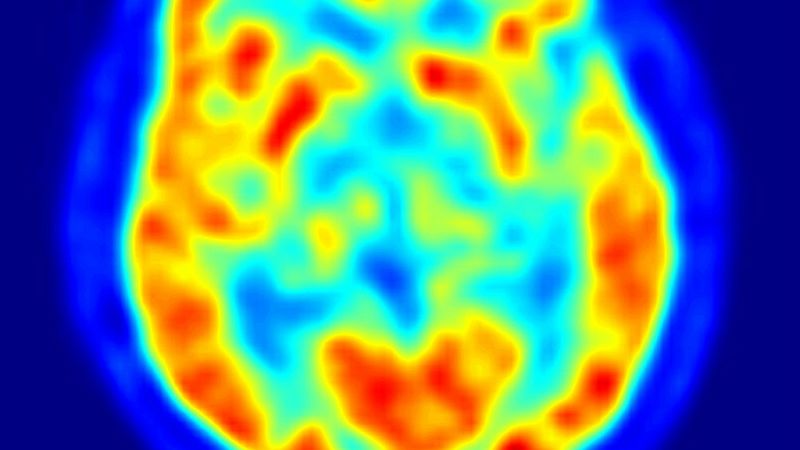

La tecnología actual permite el intercambio de información entre cerebros a distancia. El cerebro puede convertir en acción un pensamiento, incluso en personas sin movilidad, pero siempre con ayuda tecnológica. Facundo Manes, neurólogo creador de INECO Instituto de Neurología Cognitiva y coautor de El cerebro del futuro reflexiona sobre el braitnes, una especie de ordenador orgánico futuro con varios cerebros y sobre el que habrá que hacer una reflexión ética para un uso ético.